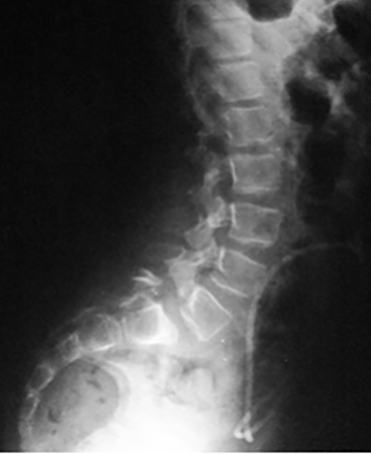

La espondilolisis es un defecto (fractura de estrés) en la pars articularis, en la región lumbar. Es secundario a microtraumatismos repetitivos, en hiperextensión repetida en ciertas actividades deportivas, como gimnasia, clavado, bailarines o futbolistas (33). Es más común en niños que en niñas, con una relación de 6:1 (Figura 2).

La espondilolistesis es cuando el defecto de la pars articularis es bilateral y se produce un desplazamiento o subluxación de la vértebra superior sobre la inferior. Es más común en la L5 sobre el sacro. La posibilidad del desplazamiento viene determinada por el potencial de crecimiento, por la presencia de cifosis lumbo-sacra y del grado de desplazamiento de una vértebra sobre la otra, al momento de la evaluación inicial. Es más frecuente el desplazamiento en pacientes mujeres jóvenes, cuando el desplazamiento inicial de una vértebra sobre la otra es mayor del 50%, cuando el tope del sacro es en forma de domo o cuando la unión lumbo-sacra es displásica. Se clasifica dependiendo de la etiología (congénita, ístmica, traumática, patológica e iatrogénica) o por el porcentaje de desplazamiento de una vértebra sobre la otra (clasificación de Meyerding). El historial mostrará un dolor de leve a moderado que se irradia a las piernas, se agrava con actividades y se alivia con el descanso. El examen físico observa una disminución de la lordosis lumbar, espasmos de los músculos isquíaticos con un caminar rígido. El diagnóstico se puede ver en radiografías lumbares laterales, pero las vistas oblicuas serán de gran ayuda en los casos más difíciles. En casos no evidentes puede ser de ayuda la cintigrafía ósea que mostrará hipercaptación en el área afectada (Figura 3). Además, la cintigrafía ósea permite saber el estadio de saneamiento. Si es agudo, habrá captación, si es crónico no habrá tanta captación. Al ser agudo, se espera mayor probabilidad de curación con tratamiento conservador y si es crónico la posibilidad de recuperación será muy pobre (34). La TC ayuda a delimitar el área más afectada. El tratamiento dependerá en el grado de desplazamiento y los síntomas. El tratamiento conservador consiste en modificar las actividades, medicación analgésica, una abrazadera y terapia física. La cirugía se indica cuando la terapia conservadora no mejora los síntomas, si hay alteraciones neurológicas o cuando el desplazamiento de una vértebra sobre otra es mayor del 50% (35). Quirúrgicamente se puede hacer una artrodesis in situ, sin instrumentación con una probabilidad de resolver el problema en un 70 % de los casos o una artrodesis instrumentada, con reducción o sin reducción del desplazamiento. La instrumentación permite corregir el defecto, aumenta la probabilidad de la fusión y mejora la mecánica espinal (Figura 4).